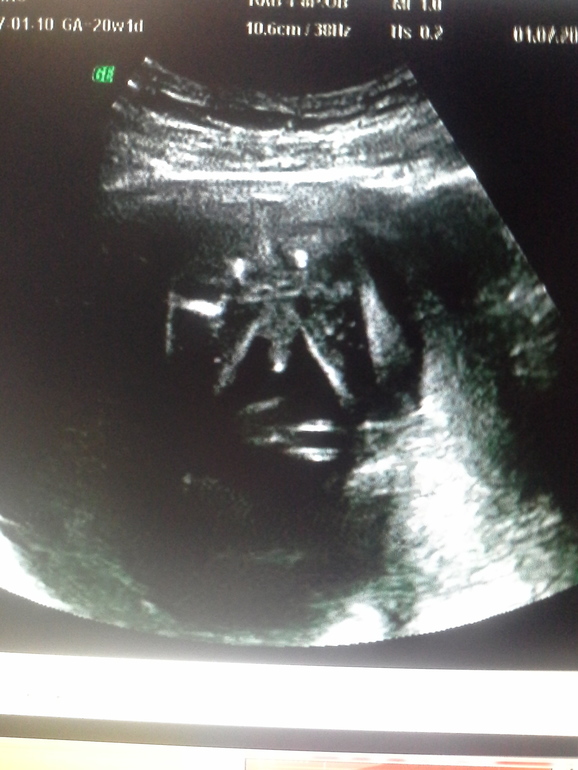

2.Были на 3 узи) Все хорошо, узистка сказала, что с прошлого раза ничего не отпало, так, что у нас все таки будет Марк)или Клим(еще спорим)))Весит мой бублик в полных 30 недель 1511гр, все отлично по замерам, напрягла шейка матки 3,5, врач сказала больше отдыхать)